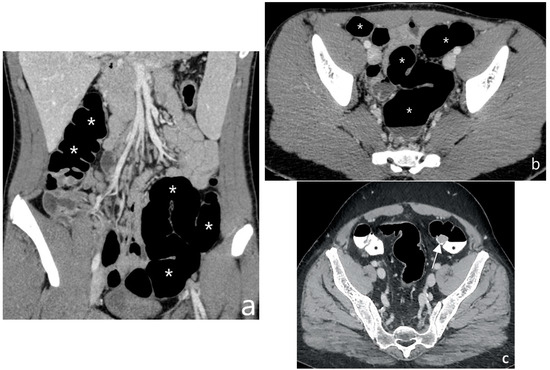

5.2. Fibro-Stenotic Subtype